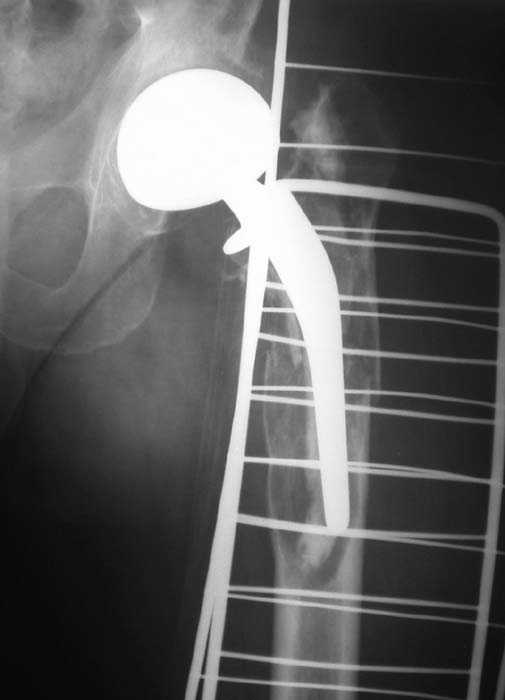

Мужчина, 39 лет.По поводу двустороннего асептического некроза головок бедренных костей последовательно выполнено тотальное эндопроезирование левого (1998 г), затем правого (1999 г) тазобедренных суставов.

С 2001 г отмечает нарастающие боли в левом бедре. Предполагается удаление протеза, удаление цемена из канала бедра, пластика дефекта бедренной кости.

Нет никакого смысла делать операцию в два этапа. С чашкой все понятно - стандартный подход с установкой пресс-фит компонента. На бедре имеет

место перипротезный перелом В3 типа - т.е. перелом вокруг ножки с ее нестабильностью на фоне выраженного остеолиза. Решение - доступ к каналу

через перелом с удалением самой ножки, костного цемента и рубцовых тканей. Установка ножки дистальной фиксации (типа Solution), длину ножки

надо определить по шаблону. Минимальный контакт ножки с интактной костью - 6-8 см. Фрагменты проксмального отдела собираются на ножке

эндопротеза, дефекты костной ткани заполняются чипсами (аллографт) и фиксируются кортикальными аллографтами, уложенными дополнительно по типу

"вязанки хвороста" серкляжом. Мы имеем 8 или 10 подобных наблюдений и результатами довольны.

Абсолютно согласен.Это проверенный путь.Единственное, под Solution надо тщательно удалить цемент из бедра куда встанет дистальная часть ножки.Иначе при установке расколите диафиз бедра.Было поначалу такое у нас.С уважением